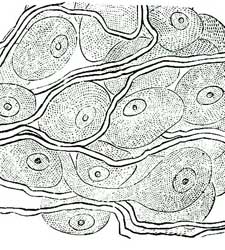

2. How many of you know what a microscope is? It is an instrument which magnifies objects, or makes them look a great deal larger than they really are. Some microscopes are so powerful that they will make a little speck of dust look as large as a great rock.

3. The Blood Corpuscles.—If you should look at a tiny drop of blood through such a microscope, you would find it to be full of very small, round objects called blood corpuscles.

4. You would notice also that these corpuscles are of two kinds. Most of them are slightly reddish, and give to the blood its red color. A very few are white.

5. Use of the Corpuscles.—Do you wonder what these peculiar little corpuscles do in the [Pg 47]body? They are very necessary. We could not live a moment without them. We need to take into our bodies oxygen from the air. It is the business of the red corpuscles to take up the oxygen in the lungs and carry it round through the body in a wonderful way, of which we shall learn more in a future lesson.

6. The white corpuscles have something to do with keeping the body in good repair. They are carried by the blood into all parts of the body and stop where they are needed to do any kind of work. They may be compared to the men who go around to mend old umbrellas, and to do other kinds of tinkering. It is thought that the white corpuscles turn into red ones when they become old.

7. The corpuscles float in a clear, almost colorless fluid which contains the digested food and other elements by which the body is nourished.

1. The blood contains very small objects called blood corpuscles.

2. There are two kinds of corpuscles, red and white.

3. The red corpuscles carry oxygen.

4. The white corpuscles repair parts that are worn.

5. The corpuscles float in a clear, almost colorless fluid, which nourishes the body.